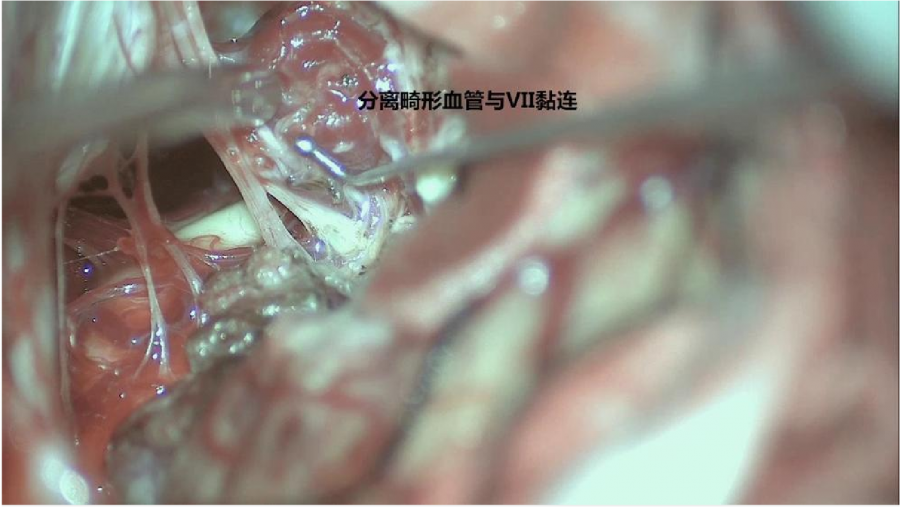

⾏左侧远外侧⼊路脑⼲⾎管畸形切除术,术中所⻅:

术后患者轻度⾯瘫House-Brackmann分级III级,可恢复。

3、脑⼲动静脉畸形⼿术切除是注意辨别供⾎动脉与引流静脉,其往往不似其他部位的动静 脉畸形,有叫粗⼤的引流静脉。术中如果不能辨清各⾎管来源与去处,往往会造成不可估量的损失。